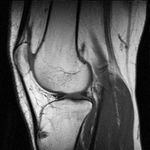

معرض الصور